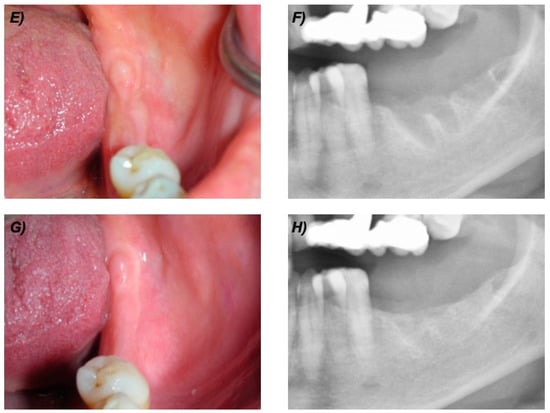

3. Results